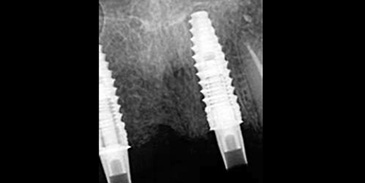

Un examen médical complet a révélé qu’il était en bonne santé, sans problèmes systémiques ou buccaux majeurs. À l’évaluation, les racines existantes des dents 12 et 21 nécessitaient une extraction. Des radiographies ont été réalisées pour évaluer le volume et la qualité osseuse, ce qui a confirmé un espace suffisant pour la pose de deux implants.

Fig. 2a : Radiographie préopératoire avec planification implantaire.

Fig. 2b : Radiographie préopératoire avec planification implantaire.